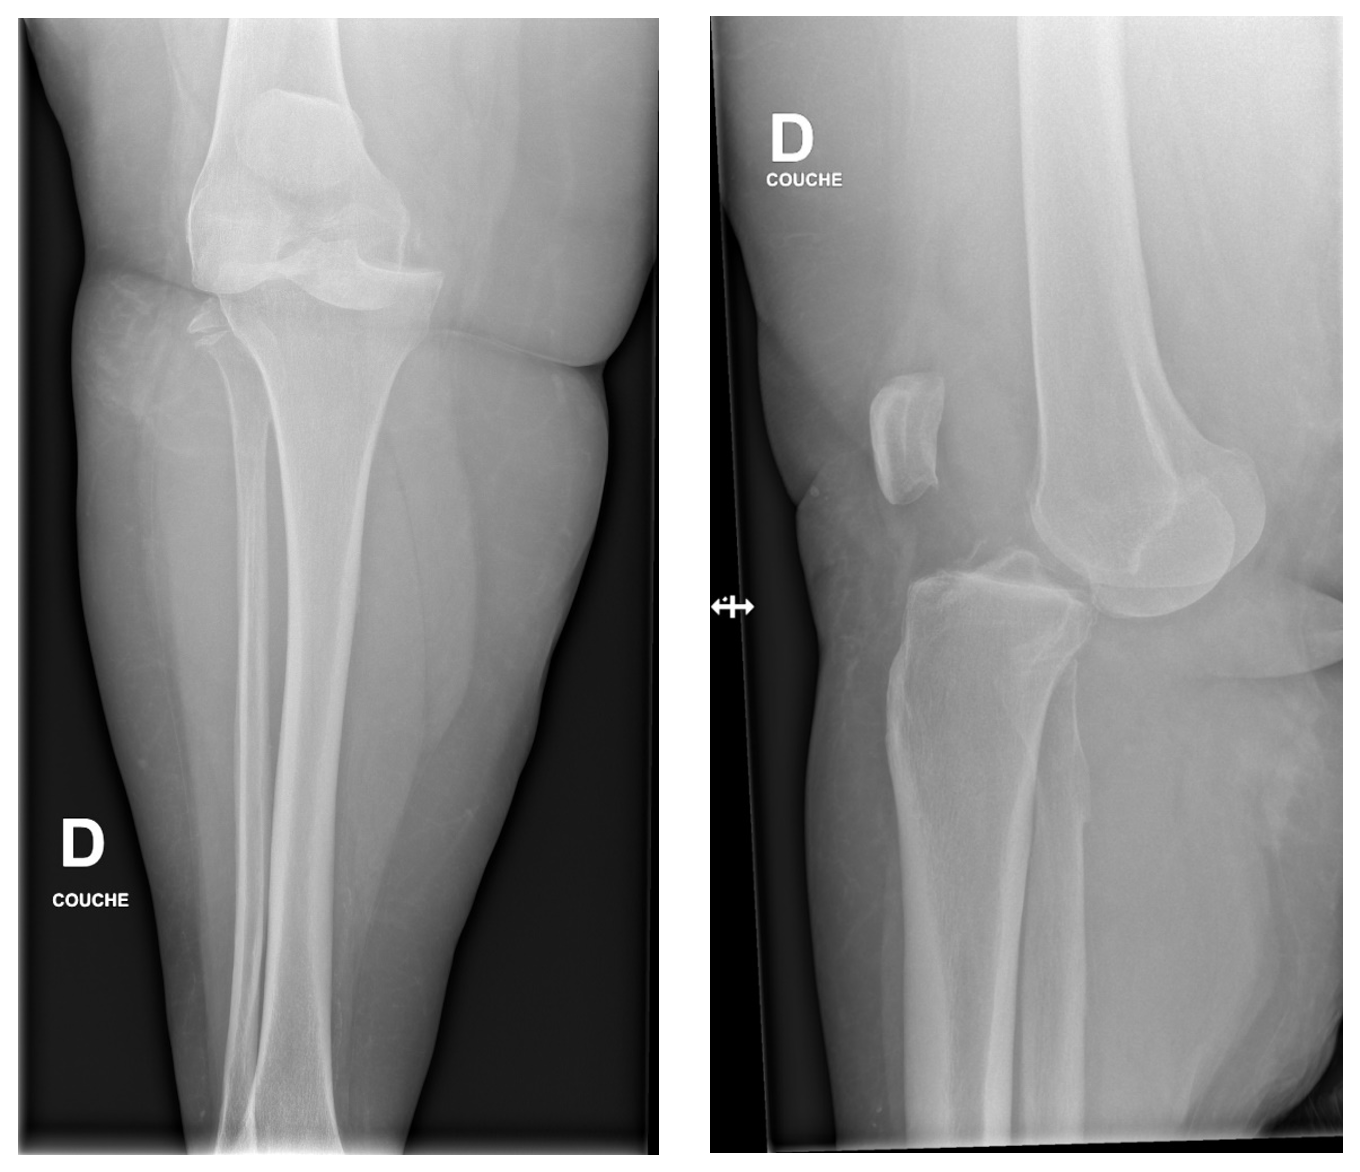

Les radiographies montrent une luxation antérieure du genou avant et après réduction.

Il existe 5 types de luxation, définie par le déplacement du tibia par rapport au fémur : postérieur, antérieur, médial, latéral, et rotatoire. Les luxations antérieures et postérieures sont les plus fréquentes.

La prises en charge consiste à effectuer rapidement une réduction fermée sous sédation-analgésie. A noter que les luxations postéro-latérales ne sont pas réductibles manuellement. Après réduction, il faut évaluer les pouls (palpés et au doppler) ainsi que le rétablissement de la congruence articulaire par de nouvelles radiographies. En cas d’absence de pouls ou d’asymétrie, un angio-CT sera effectué en urgence suivi d’une prise en charge par les spécialistes de chirurgie vasculaire. Il existe toujours des lésions ligamentaires en cas de luxation du genou. Un bilan par IRM permet de faire l’état des lieux des lésions méniscales et capsulo-ligamentaires et programmer la prise en charge orthopédique.